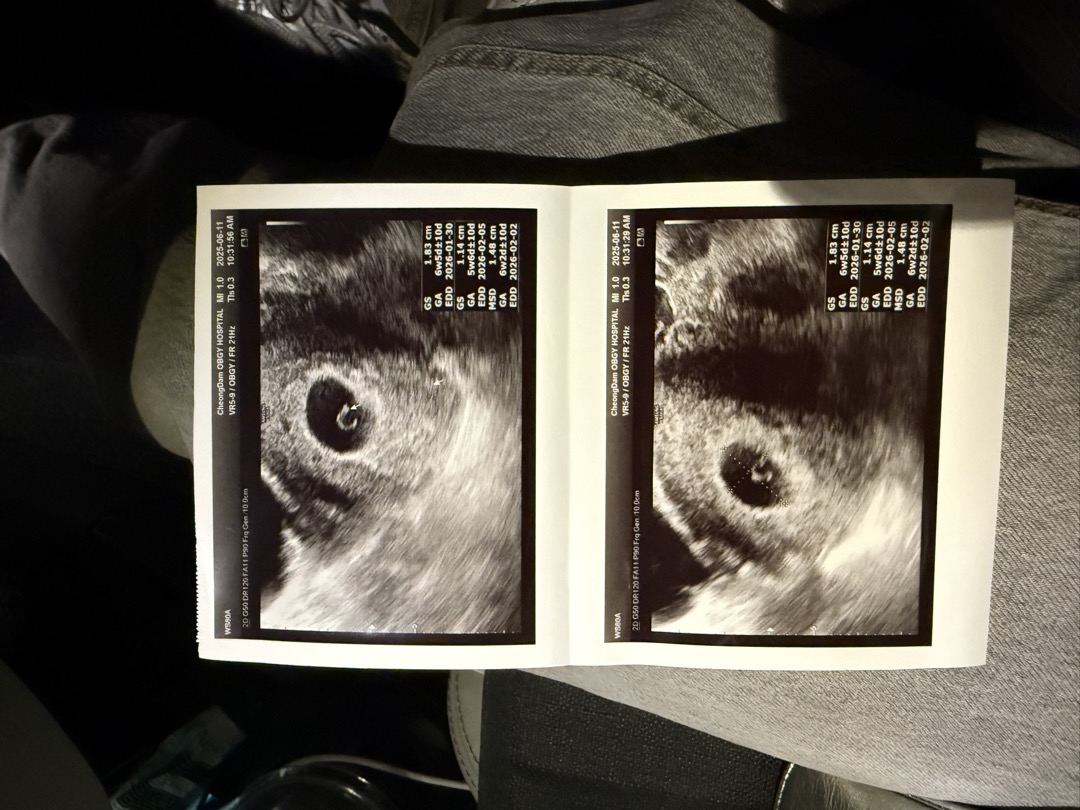

6주 2일에 심소듣구왓어용!!

2026년 2월 베동

6주0일 난황까지 보고왔어요!

심장소리 듣고싶은데 언제쯤 들을 수 있을까요..? 어제 보고 와서 2주뒤에 오라고 하셨는데 심장소리 빨리 듣고 싶어요 ㅠㅠ화살표 모양이 애기가 되는 것 같다고 하셨는데 하얀게 심장인가용?? 다들 보기에 어떠세요??

축하드랴요! 저 다이아몬드 보고 2일뒤에 심장소리들었어요 !